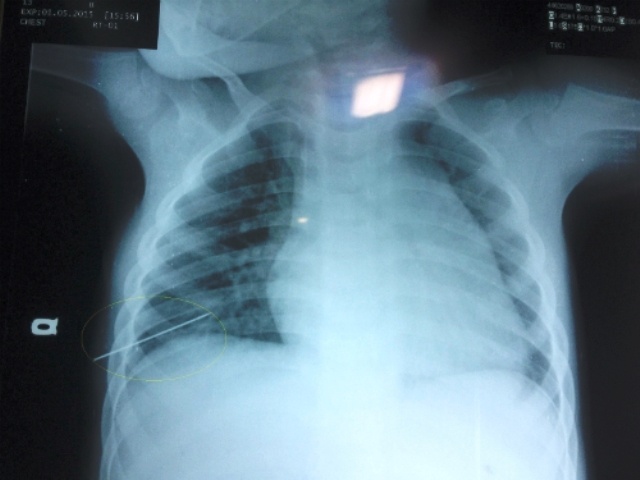

Nữ bệnh nhân bị đâm thủng phổi khi châm cứu

Nữ bệnh nhân sau khi châm cứu trở về nhà thấy khó thở, tới bệnh viện kiểm tra mới phát hiện bị tràn khí màng phổi do những mũi kim châm cứu gây ra.